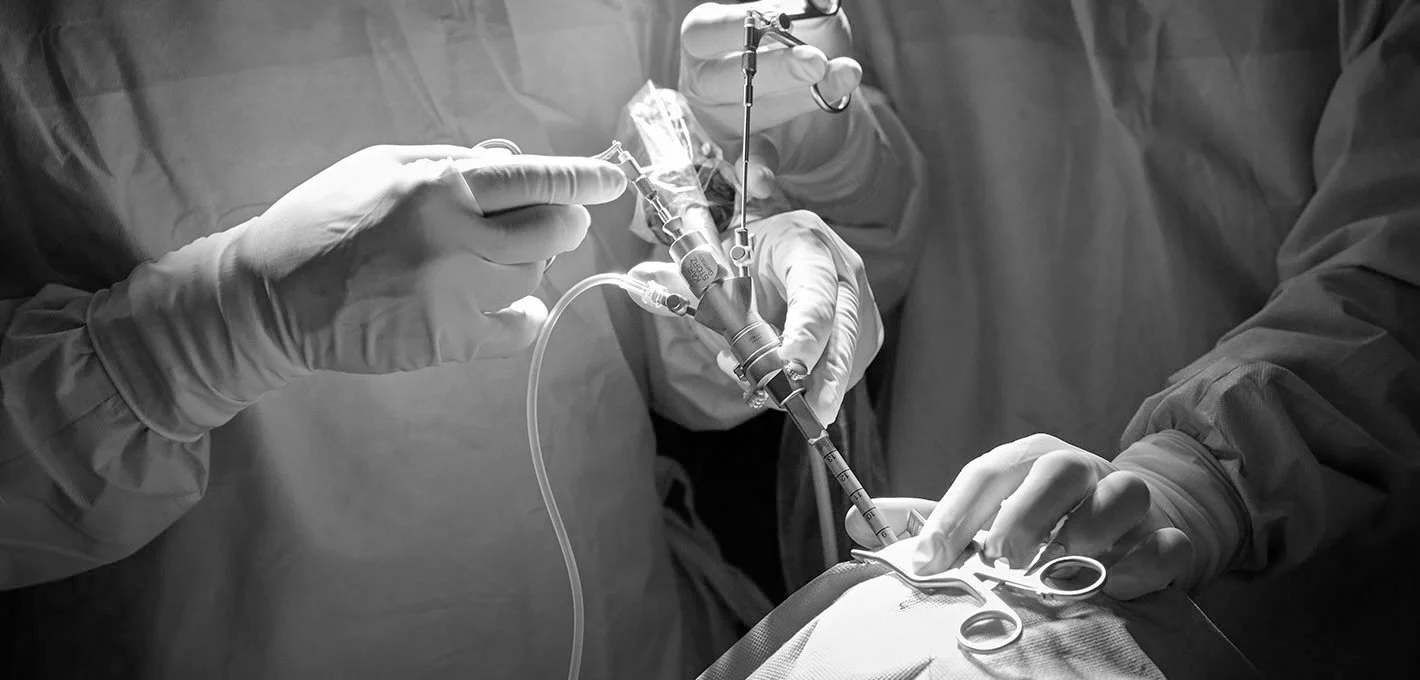

Join us at the Queen Square Simulation Centre for a hands-on neuro-oncology course focused on the practical use of modern surgical adjuncts in brain tumour surgery.

Hands-on simulation course on modern brain tumour surgery - Anatomy, techniques, and technologies.